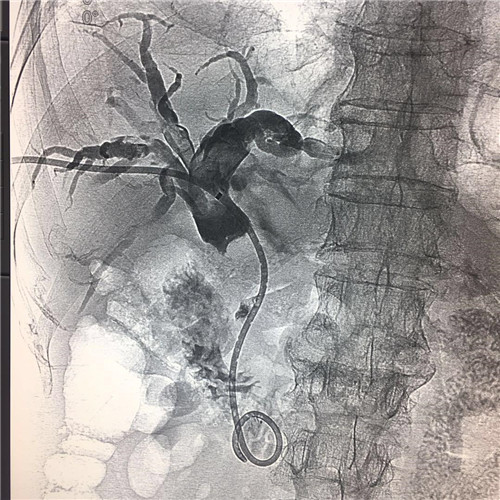

4月4日,MILAN.COM介入科成功为一位78岁高龄,胆系高位梗阻性黄疸、胆管占位病变的患者紧急成功实施了PTCD(经皮肝穿胆管引流术)。

患者全身皮肤金黄瘙痒难忍,在B超定位下行肝内胆管引流术、术后因引流不畅拔管;在胃镜下逆行ERCP胆管支架植入术,经过术者反复操作,但导丝无法通过病变段。看到患者痛苦不堪,家属迫切治疗的场面,介入科李建国主任现场会诊提出为患者在介入下行PTCD治疗的意见。术前经过讨论制定多套严密方案,与患者及家属多方沟通达成介入手术共识;术中精准定位穿刺选择不同的导丝、导管多角度旋转闭塞原地不动,时间一分一分过去......在医护人员努力下,闭塞的胆道开通了,再经球囊分段扩张病变狭窄段,内外引流管放置顺利300余毫升的黑褐色胆汁流出......

在护理人员精心的配合下,手术历时30余分钟圆满成功,彻底解决了患者梗阻性黄疸引发的皮肤黄染,保护了肝功能。

顺行开通高位胆管梗阻性黄胆经皮肝穿胆管引流术优势明显